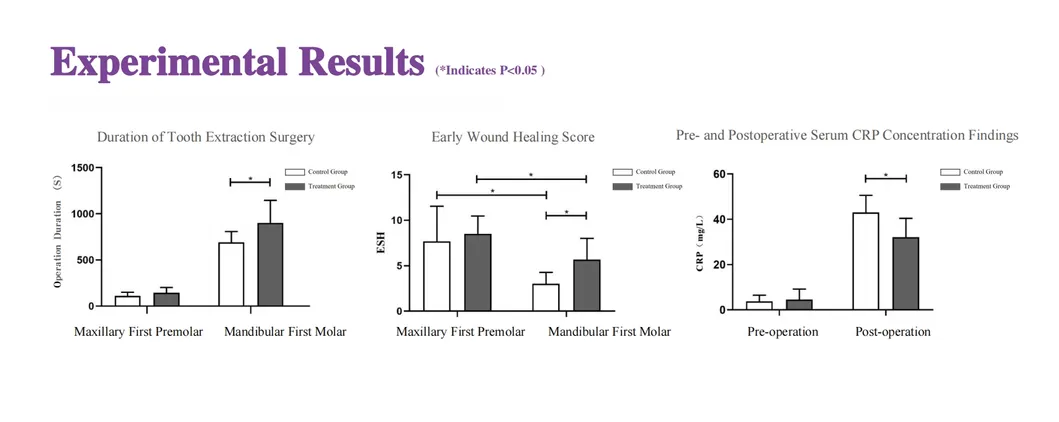

This study evaluated the effectiveness of state-of-the-art dental tools for veterinary use. The treatment group utilized the revolutionary Pneumatic Dental Elevator Kit. Critical factors observed included physiological parameters, intraoperative complications, extraction duration, and socket damage. Rigorous statistical analysis highlights the superior performance of these advanced tools.